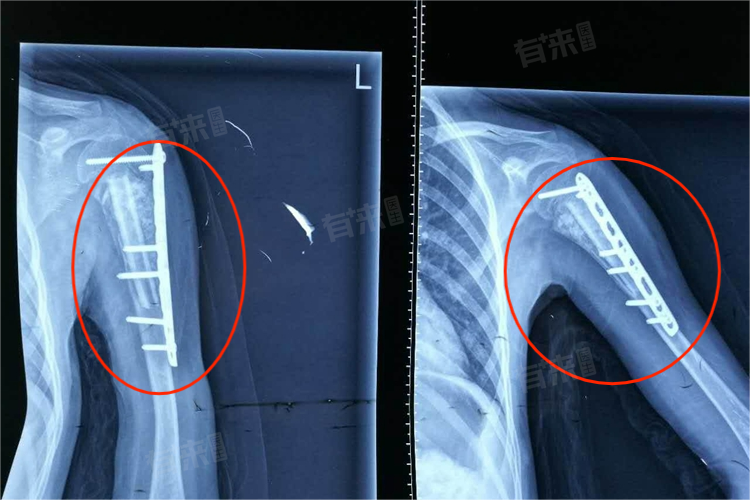

- 骨折风险:由于左肱骨在运动中承受着较大的负荷,因此容易发生骨折,特别是肱骨上端与肩胛骨交界处和肱骨下端与尺骨、桡骨交界处,都是骨折的易发部位。

- 神经血管损伤:左肱骨后侧存在桡神经沟,桡神经和肱动脉都会从这条神经沟经过,当左肱骨发生骨折时,有可能对桡神经和肱动脉造成损伤。